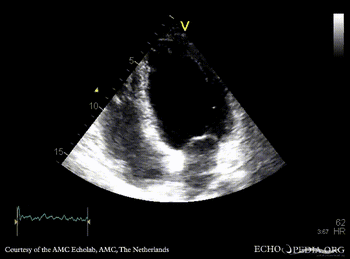

Infarction of posterior and inferior wall

PLAX: dilated left ventricle, akinesia of posterior wall PSAX: akinesia of posterior and inferior wall